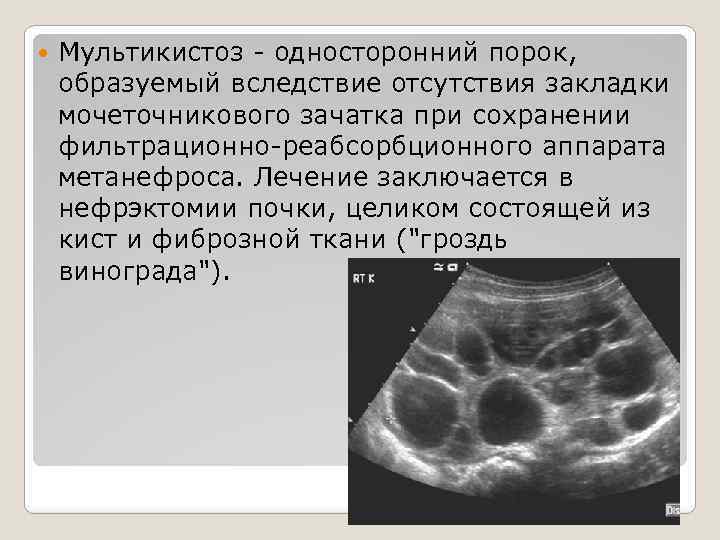

Мультикистоз - односторонний порок, образуемый вследствие отсутствия закладки мочеточникового зачатка при сохранении фильтрационно-реабсорбционного аппарата метанефроса. Лечение заключается в нефрэктомии почки, целиком состоящей из кист и фиброзной ткани ("гроздь винограда").

Мультикистоз - односторонний порок, образуемый вследствие отсутствия закладки мочеточникового зачатка при сохранении фильтрационно-реабсорбционного аппарата метанефроса. Лечение заключается в нефрэктомии почки, целиком состоящей из кист и фиброзной ткани ("гроздь винограда").